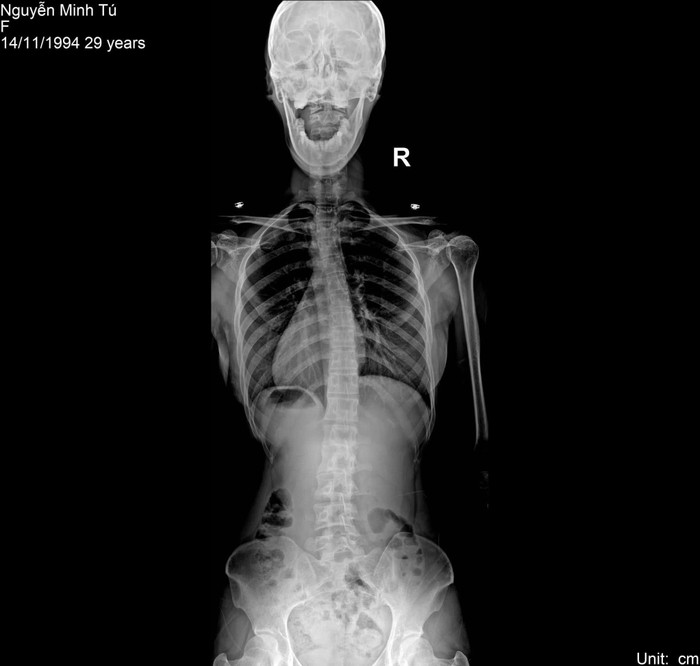

Siêu mẫu Minh Tú vừa có những trải lòng đầy xúc động về chuyện con cái. Cô tiết lộ đang đối mặt với nhiều căn bệnh nghiêm trọng gồm thoái hóa cột sống, mất xương và các vấn đề liên quan khác. Chính những thách thức này đã khiến Minh Tú chưa thể mang thai. Đồng thời làm dấy lên lo ngại về khả năng ảnh hưởng đến sức khỏe nếu cô có con trong tương lai.

Minh Tú chia sẻ: "Sự thật là Tú cũng chưa có em bé, và không phải Tú bỏ bê không chăm sóc bản thân mình đâu ạ. Trong nửa đầu năm 2024, Tú đang phải đối mặt với những thách thức từ bên trong, liên quan đến sức khỏe cột sống, thoái hóa và mất xương. Điều này đồng nghĩa với việc trong tương lai, Tú có thể gặp khó khăn trong sinh hoạt hàng ngày, đi lại hoặc cả khi có em bé".

Những căn bệnh mà Minh Tú đang đối mặt, như thoái hóa cột sống và mất xương đều không hiếm gặp. Đặc biệt trong thời đại mà áp lực công việc và lối sống dễ dẫn đến tình trạng này. Tuy nhiên, căn bệnh này có ảnh hưởng lớn đến chất lượng cuộc sống, sinh hoạt hàng ngày và khả năng sinh sản.

Theo tìm hiểu các bệnh lý liên quan đến cột sống, thoái hóa và mất xương không chỉ làm suy yếu cơ thể mà còn ảnh hưởng trực tiếp đến việc mang thai. Khi người mẹ mang thai, trọng lượng thai nhi sẽ tạo áp lực lớn lên cột sống vốn đang suy yếu, có thể gây ra các biến chứng nguy hiểm cho cả mẹ và bé. Ngoài ra, một số bệnh lý về xương khớp có khả năng liên quan đến yếu tố di truyền, làm tăng nguy cơ con sinh ra cũng mắc bệnh.